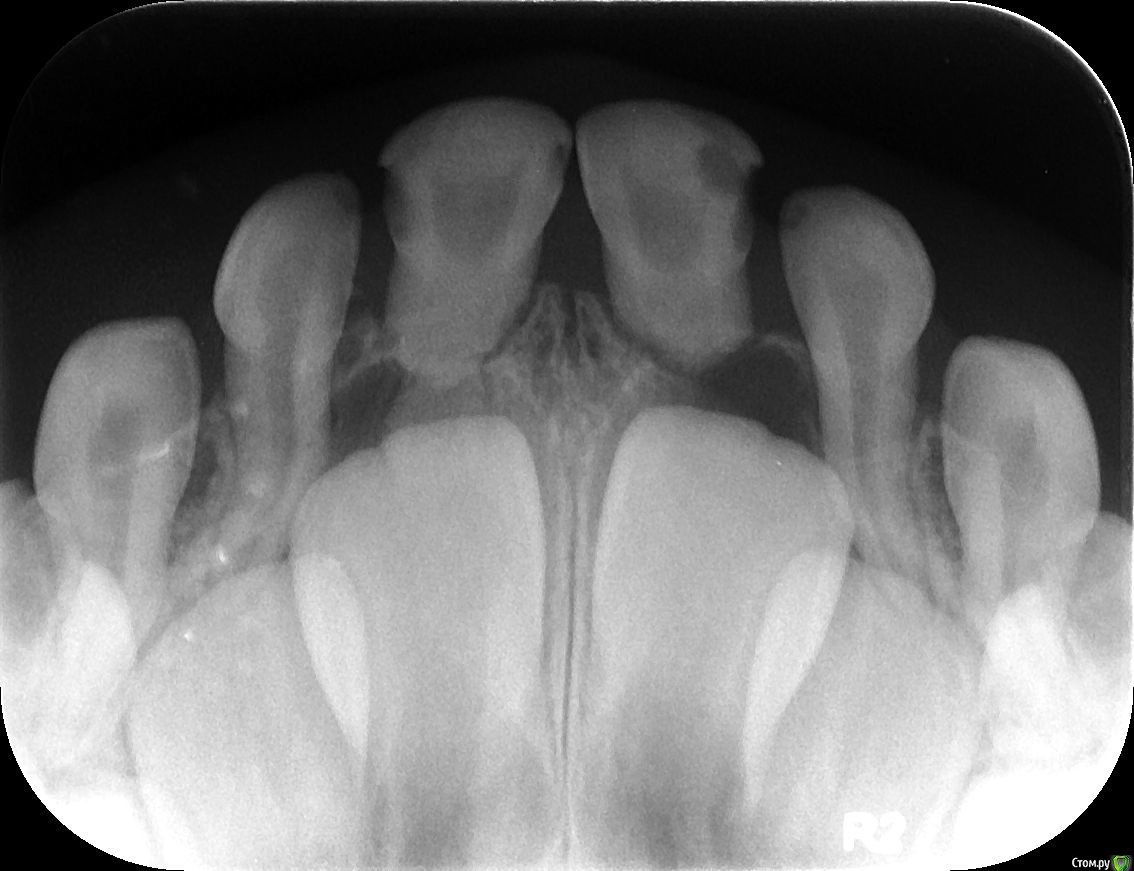

Elena Bundren Опубликовано 27 июня, 2018 Поделиться Опубликовано 27 июня, 2018 Здравствуйте!Пришли с 5-летним ребенком к стоматологу. Он обнаружил 12 кариесов, сказал, на несколько зубов надо ставить серебренные коронки.Моляр справа внизу подлежит удалению, так как под ним инфекция.И все это хорошо бы сделать под общей анестезией за один раз.Вопросы уважаемым докторам, сколько, по-вашему, зубов реально подлежит лечению, и есть и возможность, на ваш взгялд, сохранить моляр, если да, то какое нужно лечение.Также, каково ваше мнение об общей анестезии для ребенка 5 лет. Ссылка на комментарий

St. Опубликовано 27 июня, 2018 Поделиться Опубликовано 27 июня, 2018 Добрый день. Зубы действительно в очень плохом состоянии и практически на всех между зубами есть кариес.Металлические коронки у детей это хорошо, они позволяют надежно провести лечение сильно разрушенных зубов и не опасаться сколов и вторичного кариеса. Ссылка на комментарий